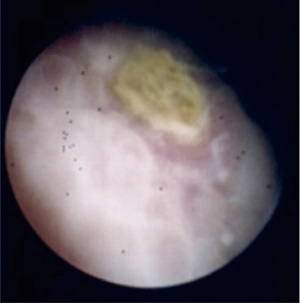

A 55-year-old Caucasian male presented to the emergency room with acute lower abdominal pain and a 1-week history of refractory constipation. He did not report stranguria, pneumaturia, or fecaluria. Past medical history was unremarkable except for multiple recurrent episodes of acute sigmoid diverticulitis. Blood pressure was 130/78 mmHg, heart rate 100 bpm, and oxygen saturation 97% on room air. Body temperature was normal. Physical exam showed mild abdominal distension and tenderness in the lower abdominal quadrants. Abdominal ultrasound showed a small fluid collection in the left lower quadrant. Blood tests showed increased C-reactive protein (13.7 mg/dL) and white blood count (12,500/µL with 86% neutrophils). Plain abdominal X-ray did not reveal free air nor air-fluid images. A CT scan showed a complicated distal left colon diverticulitis with a long segment (7 cm) wall thickening, luminal narrowing (Figure 2A), and multiple perivisceral abscesses (Figure 2B). Moreover, air bubbles inside the bladder were visible (Figure 3), raising the suspicion of a colovesical fistula (Figure 4A,4B). The patient underwent a cystoscopy, which confirmed the presence of a fistula on the posterior-lateral wall of the bladder 2 cm above the vesical trigone (Figure 5). A colonoscopy ruled out the presence of malignancy. The patient was treated with a Foley catheter, clear liquid diet, and broad spectrum antibiotics. Blood tests normalized in a few days, and the patient was discharged home. Readmission for surgical treatment was planned in 3 weeks.